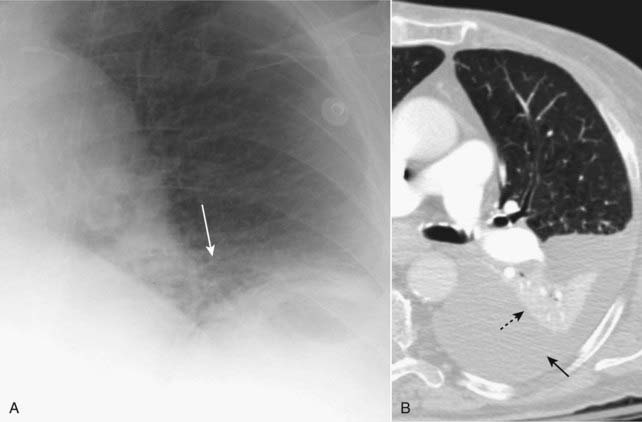

image

Figure 5-9 Atelectasis and effusion in balance, an ominous combination.

There is complete opacification of the right hemithorax. There are neither air bronchograms to suggest pneumonia nor any shift of the trachea (solid black arrow) or heart (solid white arrow). The absence of any shift suggests the possibility of atelectasis and pleural effusion in balance, a combination that should raise suspicion for a central bronchogenic carcinoma (producing obstructive atelectasis) with metastases (producing a large pleural effusion).

image Lower lobe atelectasis (Fig. 5-12)

On the frontal radiograph:

Both the right and left lower lobes collapse to form a triangular density that extends from its apex at the hilum to its base at the medial portion of the affected hemidiaphragm.

Elevation of the hemidiaphragm is seen on the affected side.

The heart may shift toward the side of the volume loss.

On the right (only), there is a downward shift of the minor fissure.

On the lateral radiograph:

There is both downward and posterior displacement of the major fissure until the completely collapsed lower lobe forms a small triangular density at the posterior costophrenic angle.

Figure 5-12 Left lower lobe and right lower lobe atelectasis.

A, A fan-shaped area of increased density behind the heart is sharply demarcated by the medially displaced major fissure (solid black arrows) representing the characteristic appearance of left lower lobe atelectasis. B, On the lateral view, the major fissure (solid white arrows) is displaced posteriorly. The small triangular density in the posterior costophrenic sulcus is in the characteristic location for left lower lobe atelectasis on the lateral projection. C, In a different patient there is a fan-shaped triangular density in the right lower lobe bounded superiorly by the major fissure (solid white arrow). Notice how the unaerated lower lobe silhouettes the right hemidiaphragm (solid black arrow).

imageIn the critically-ill patient, atelectasis occurs most frequently in the left lower lobe.

Always check that the left hemidiaphragm is seen in its entire extent through the heart since left lower lobe atelectasis will manifest by disappearance (silhouetting) of all or part of the left hemidiaphragm (see Fig. 5-12).